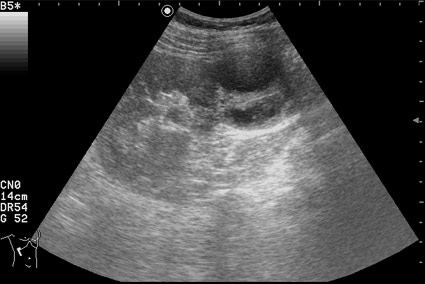

Сонограмма правой почки у женщины 42 лет. Женщина болеет сахарным диабетом, профилактический осмотр.

Как трактовать выявленные изменения? Какова тактика врача УЗД в данной ситуации?

по Bosniak-type3-indetrminate lezion- показана биопсия

Почечно-клеточный рак, тип "опухоль в кисте" ?

RCC. Тип "опухоль в кисте".